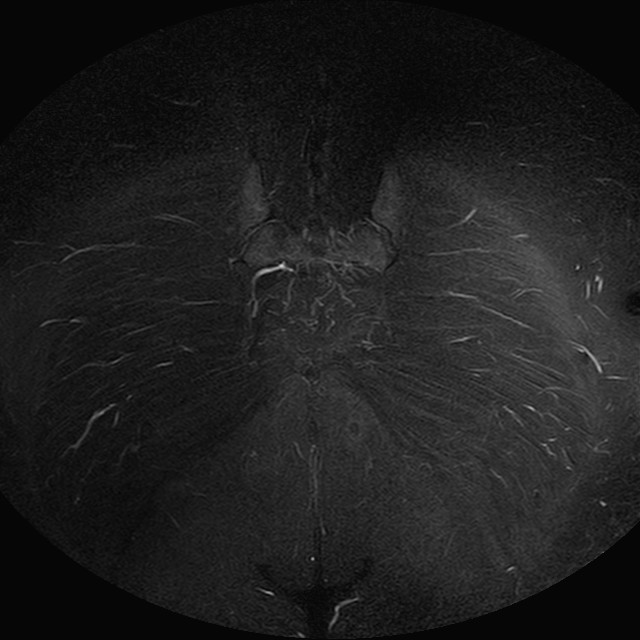

eSTIR

Evidenti e simmetriche alterazioni osteofitosiche in regione coxo femorale con riduzione delle rime articolari. Degenerazione completa del cercine glenoideo. Non attuali segni di versamento articolare. Non segni di edema osseo che escludono attuale algodistrofia od osteonecrosi. Lieve e simmetrica riduzione del trofismo della muscolatura glutea.